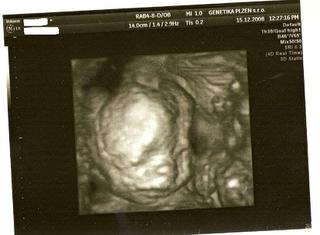

@m.evzenie, o fotečky jsem si vždy říkala. Taky jich mám hromadu 🙂 Třeba z velkého UTZ ve 20tt mám 8 fotek 🙂

Ahoj holky 🙂 , tak včerejší kontroly ok 😵 , genetika ok 😵 (3* hurá, vyhnuli jsme se plodovce ), utz srdíčka taky ok 😵 a na 3d fotce máme vyfocenou pipinku, takže u nás je jasno 😀 . a dr. se s tipem v tom 13.tt týdnu nemýlil 😎 i . Jdu dočíst 😉 .